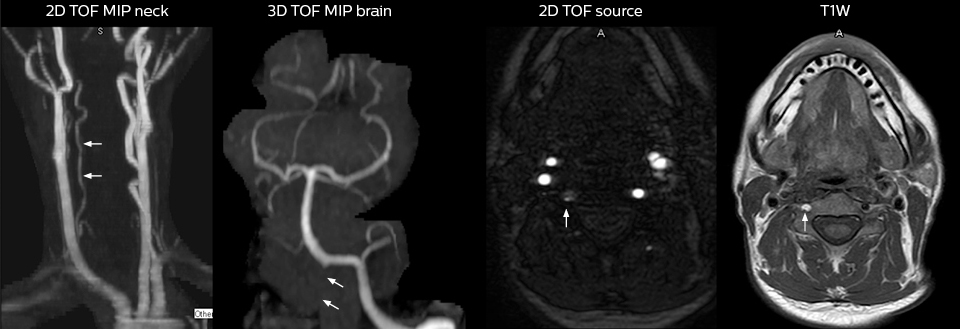

“For the thoracic and cervical spine routine non-contrast exam, for example, we perform one mDIXON T2 TSE sequence, which provides us with two outputs: the fat-and-water-together T2-weighted images, as well as the water-only sagittal T2-weighted images. And then we also perform an axial gradient echo exam.”

Cervical spine routine exam

This patient presented with headache that was worse with neck flexion and we see a Chiari 1 malformation with low-lying cerebellar tonsils as well as some degenerative cervical thrombolytic change.